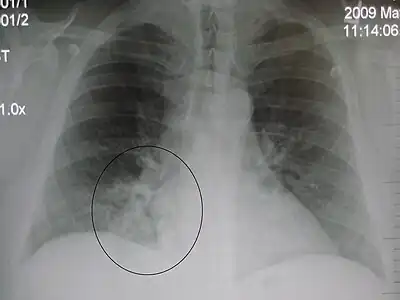

AP CXR showing left lower lobe pneumonia associated with a small left sided pleural effusion -

AP CXR showing right lower lobe pneumonia -

AP CXR showing pneumonia of the lingula of the left lung -

Right upper lobe pneumonia as marked by the circle. -

Left upper lobe pneumonia with a small pleural effusion.